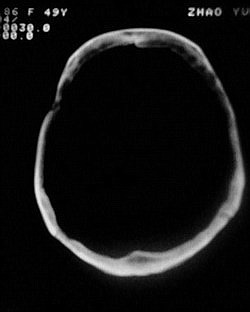

患者/49y/ 女/4年前有脑梗, 现因右侧肢体无力来院做ct扫描 ! 老师们看看这骨头有事吗?钙化点是什么原因呀??

1.颅骨对称性、形态规整性增厚,应属发育异常。四叠体池左后侧单发点状钙化,无其他阳性表现,多属正常,不需要过多关注。

2、颅骨形态规整性的增厚,密度增高,有无骨髓方面的疾病,建议骨髓穿刺。

可能为颅骨内板增生症,以额骨多见,常见于女性.多无临床意义.部分病人可有头痛.可找相关资料看看.

2.颅骨内外板广泛性增厚,板障狭窄甚至消失,双侧对称。无明显相应临床症状。考虑“泛发性骨皮质增厚症”。可进一步检查下颌骨及管状骨骨干。(下颌骨骨小梁增多、密集,密度增高亦为本病特点,管状骨骨干皮质向内增厚引起骨皮质厚度增加,骨密度增浓、髓腔狭窄但不消失,骨干周径较少增加)。与石骨症鉴别,后者很少影响颅盖骨和下颌骨,管状骨改变主要累及干骺端和骨骺,而骨干皮质较少增厚,椎体和髂骨翼有特征性表现。

“泛发性骨皮质增厚症,又称骨内膜增生症(endosteal hyperostosis):分为常染色体隐性遗传性疾病(van buchem)和常染色体显性遗传性骨硬化症(worth病)。后者更少见,亦较轻。两者的病理上均为骨内膜 成熟的板状新生骨形成,髓腔变窄。颅骨、颅底骨 、下颌骨,肋骨、四肢骨及骨盆骨、脊柱均可见骨内膜增生,髓腔变窄或消失,但骨外径不加大,骨骺不累及。”